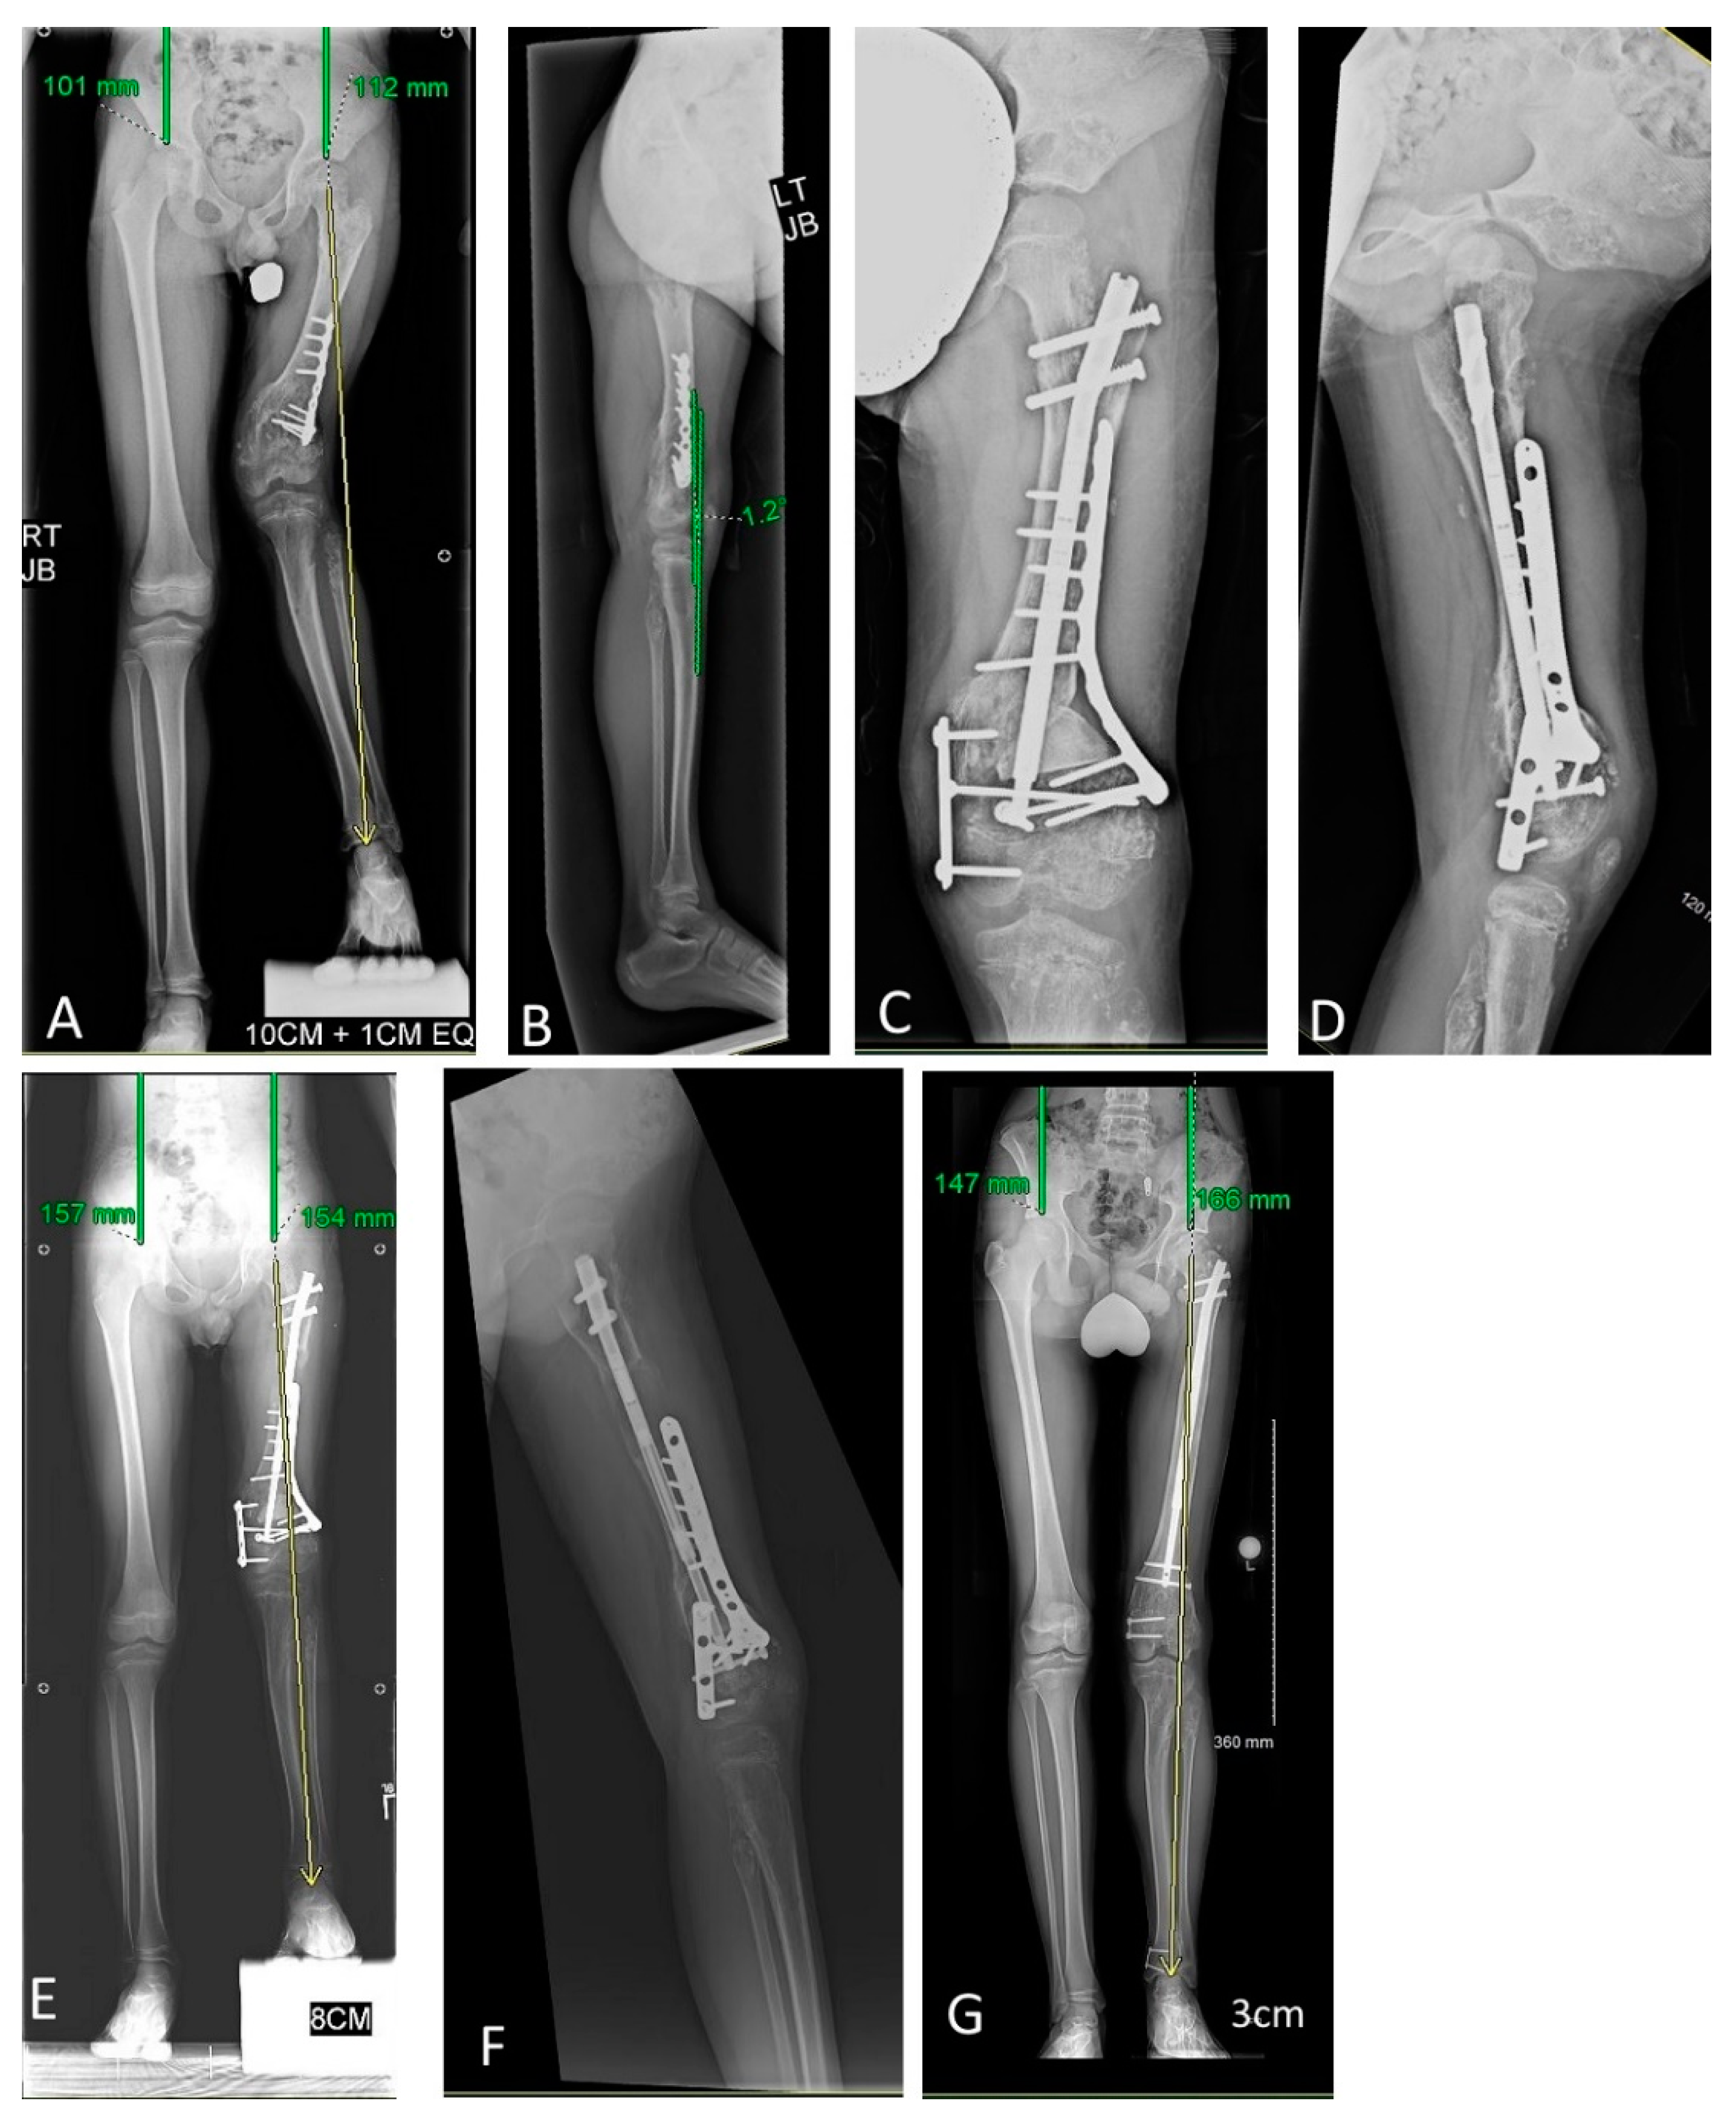

Figure 2. Limb lengthening episode complicated by mismatched hardware and osteotomy distraction. This figure portrays Patient 5’s lengthening experience. A 7-year 3-month-old male with enchondromatosis affecting all long bones of both legs, most severely the right femur and tibia. The initial diagnosis was Ollier’s disease. (A) His first lengthening was performed to address left greater than right leg discrepancy of 114 mm. (B) He was managed with right femur osteotomy and implantable lengthening nail (Precice). The angled femoral neck screws are anterior to the nail and were placed to prophylactically reinforce the femoral neck. The proximal and distal cross-locking screws are intralesional. (C) The nail eventually elongated approximately 40 mm, while the osteotomy gap elongated only approximately 12 mm, which along with the noticeable difference of the distal cross-lock screw position relative to the condyles, indicated the distal intralesional fixation provided insufficient purchase. The patient had never experienced any pain or other complications other than the mismatch between nail elongation and osteotomy distraction. (D) Given there was no need for emergent intervention, the patient was given a consolidation period of one year and lengthening was attempted again. A longer nail was inserted and cross-locking screws were placed on either side of the distal physis. (E) Premature consolidation and nail migration was redemonstrated; there was a nearly 2:1 nail:osteotomy elongation mismatch. (F) Fixation was changed to a shorter nail which, although allowing only one distal cross-locking screw, it was placed in extralesional bone and intra-operatively felt stronger during drilling and insertion. (G) The nail and osteotomy gap then lengthened proportionately; he eventually achieved 47 mm of distraction and was stopped due to proximal screw migration. While this patient remained under postoperative lengthening observation, his diagnosis evolved from Ollier’s disease to Maffucci’s syndrome, based on the development of hemangiomas.